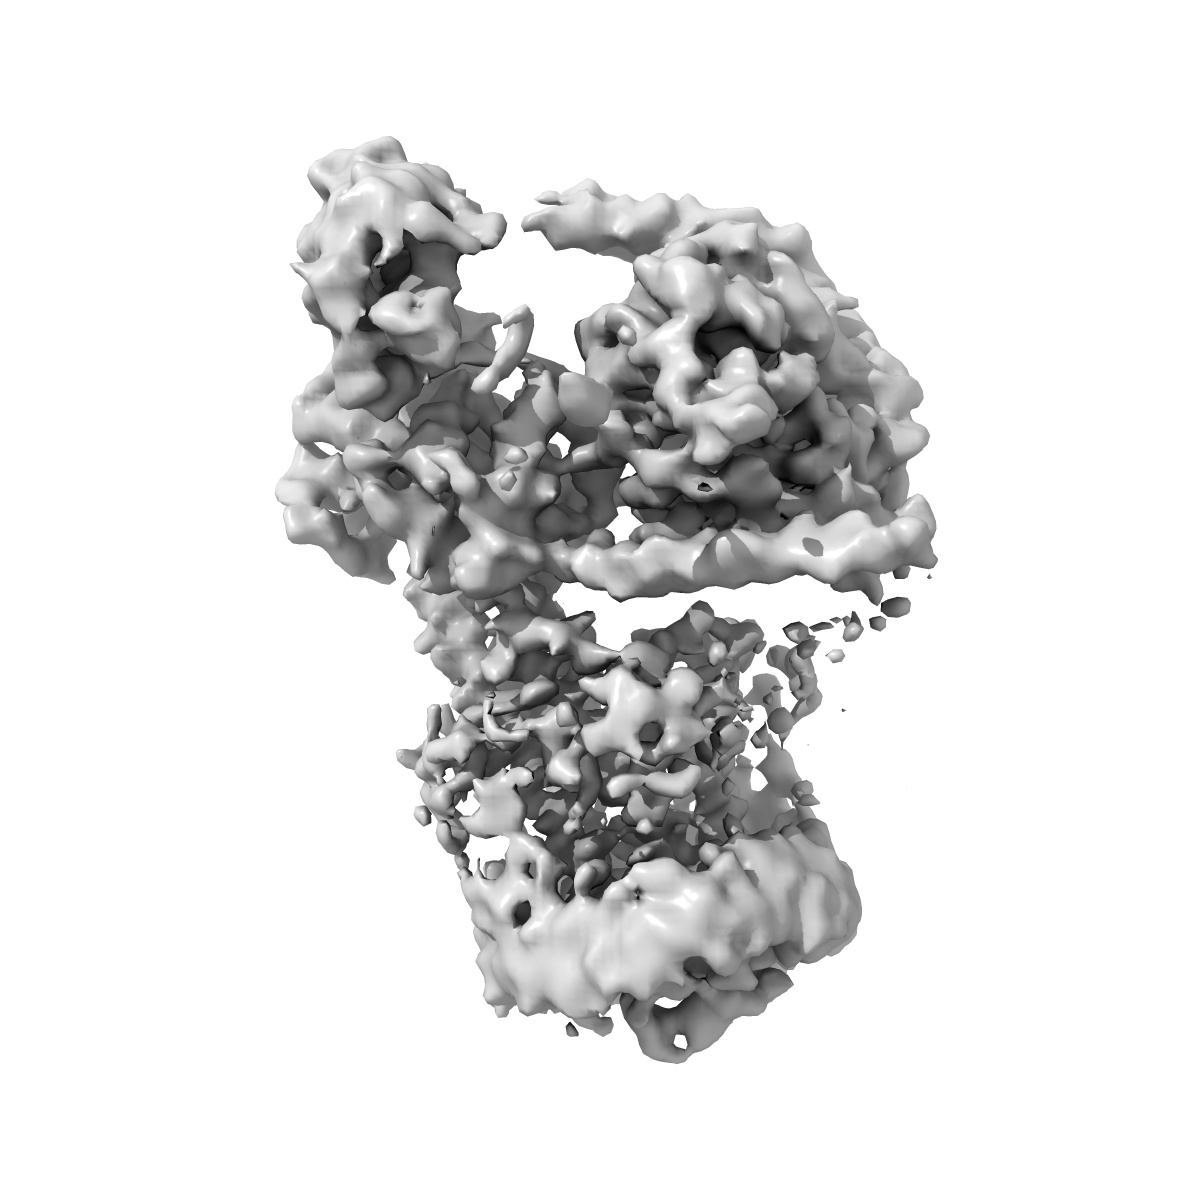

CryoEM structure of beta-2-adrenergic receptor in complex with nucleotide-free Gs heterotrimer (#20 of 20)

Sample: Complex of beta-2 adrenergic receptor and Gs heterotrimer

Fitted models: 8gej

Time-resolved cryo-EM of G-protein activation by a GPCR.

PUBMED: 38480881